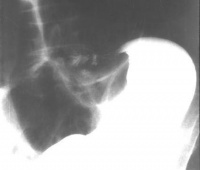

肠套叠空气灌肠可见肠套叠处呈“杯口”状改变。

肠套叠